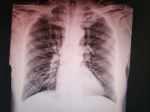

1例重癥肺炎并呼吸衰竭 關(guān)鍵疾?。?a href="http://m.akellydesign.com/tags/so/呼吸衰竭-4-1.html" target="_blank">呼吸衰竭肺炎 現(xiàn)病史【一般資料】女性,59歲歲,農(nóng)民【主訴】間斷發(fā)熱半月,呼吸困難半天【現(xiàn)病史】半月前受涼后出現(xiàn)發(fā)熱,體溫38.4℃,無咳嗽、咳痰,無頭痛、惡心,無腹痛、腹瀉,無尿頻、尿急、尿痛,自服“尼美舒利”,體溫降至正常。12天前再次發(fā)熱,體溫38℃,口服“尼美舒利”后,體溫正常,未再進(jìn)一步診治。半天前出現(xiàn)胸悶、氣短,口服“麝香保心丸”,癥狀不緩解,并出現(xiàn)嘔吐,嘔吐物為胃內(nèi)容物,急診至縣中醫(yī)院查胸部CT:兩肺大片高密度影,急來我院。【既往史】20余年曾因“甲狀腺結(jié)節(jié)”手術(shù)治療。“2型糖尿病”10余年,應(yīng)用...